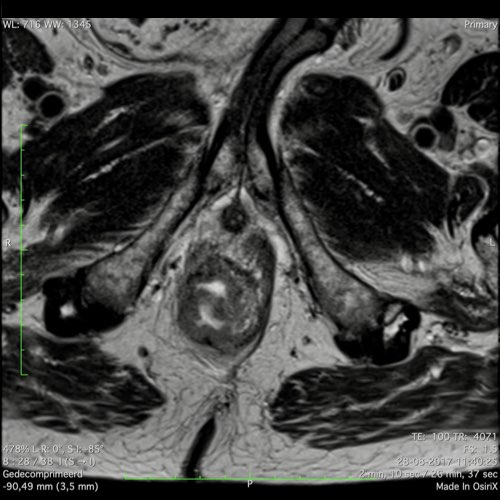

Hình ảnh

Các hình ảnh được cung cấp cho thấy ung thư biểu mô tế bào nhẫn với tình trạng dày lan tỏa thành trực tràng, hình ảnh bia bắn điển hình, và sự xâm lấn mỡ mạc treo trực tràng.